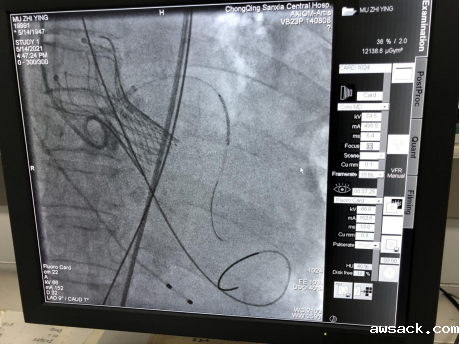

2021年5月14日,心脏大血管外科成功为两名70多岁高龄主动脉瓣重度狭窄患者分别实施了体外循环支持下经导管主动脉瓣置换术(Transcatheter Aortic Valve Replacement,TAVR)和同期经皮冠状动脉介入治疗( percutaneous coronary intervention,PCI)+TAVR,两台手术的顺利完成,再次为我院TAVR新技术积累了宝贵的经验。

5月14日12点,患者转入介入室,在多学科专家团队共同协作下,历时7小时成功为两名主动脉瓣患者完成手术。这是我院首次采用体外循环下实施TAVR,体外循环阻断人体循环,为心脏保证停跳过程中人体的血液循环,提供无血手术野,进行心操作。手术方式为经股动脉送入介入导管,将人工心脏瓣膜输送至主动脉瓣区打开,从而完成人工瓣膜置入。